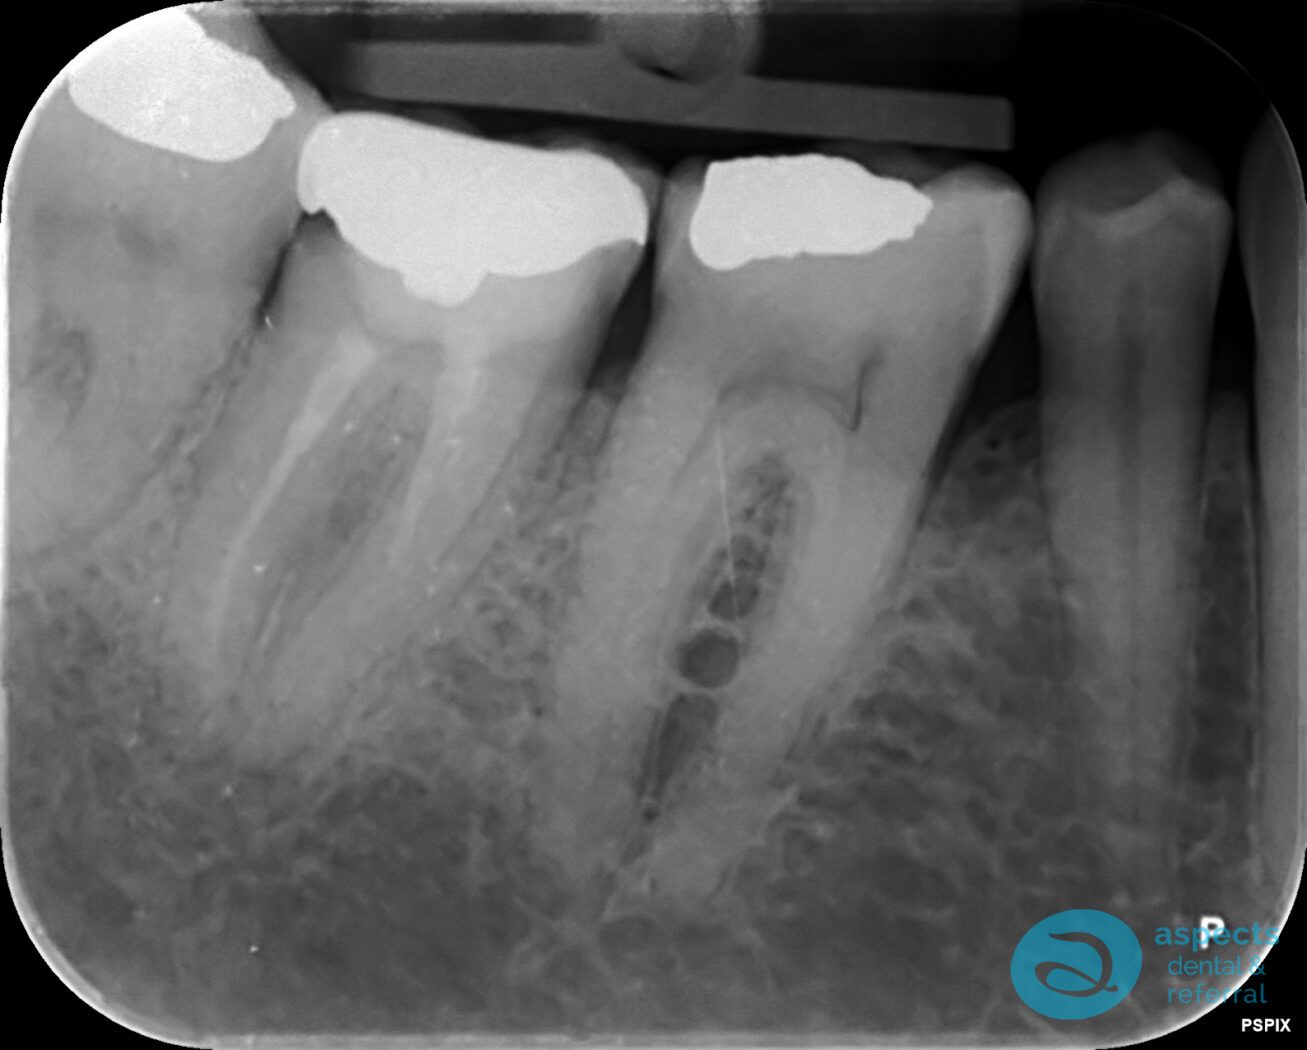

Our Dental Patient presented with a failing long-term Dental Crown and significant loss of tooth structure, rendering the tooth non-restorable. The tooth was subsequently extracted.

Before Tooth Extraction & Dental Implant Xray